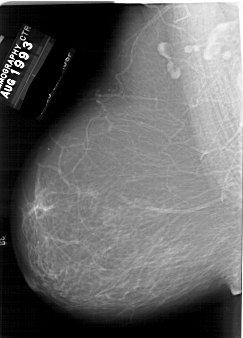

A_1857_1.LEFT_MLO

LEFT_MLO LINES 6421 PIXELS_PER_LINE 4606 BITS_PER_PIXEL 12 RESOLUTION 43.5 NON_OVERLAY

FILE: A_1857_1.RIGHT_MLO.OVERLAY

TOTAL_ABNORMALITIES 1

ABNORMALITY 1

LESION_TYPE MASS SHAPE IRREGULAR MARGINS ILL_DEFINED

ASSESSMENT 4

SUBTLETY 3

PATHOLOGY BENIGN

TOTAL_OUTLINES 1

BOUNDARY